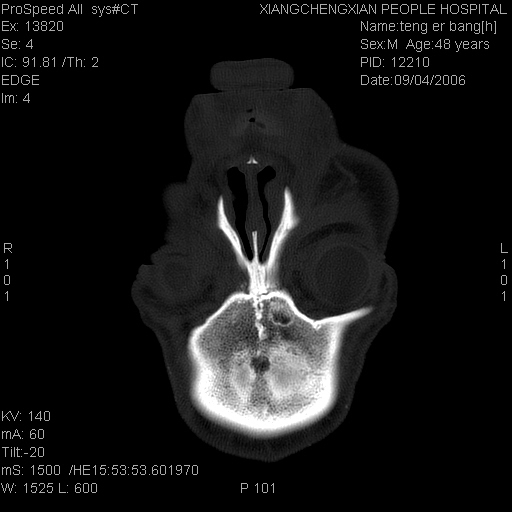

患者,男,以头面部外伤后头疼1小时为主诉入院,患者1小时前被他人打伤头部及左侧面部,眼睑无水肿,左侧面部肿胀压疼,未触及骨擦音。专科检查:耳鼻喉未见异常。

ct:平扫+冠扫:双侧鼻骨对比,冠扫s6#示右侧鼻骨尖部可见线状低密度影,边缘光滑,并见硬化.软组织未见肿胀.

诊断意见:鼻额缝(鼻骨与上颌骨额突缝),但个别同志认为是骨折.因此请同行们会诊.多谢了!

正常鼻颌缝。软组织无肿胀。鼻腔无积液积血。鼻骨光滑规整无中断。均不支持骨折。

正常的,双侧对称.边缘光整,且逢等宽.

正常鼻颌缝。软组织无肿胀。鼻腔无积液积血。鼻骨光滑规整双侧对称。均不支持骨折。